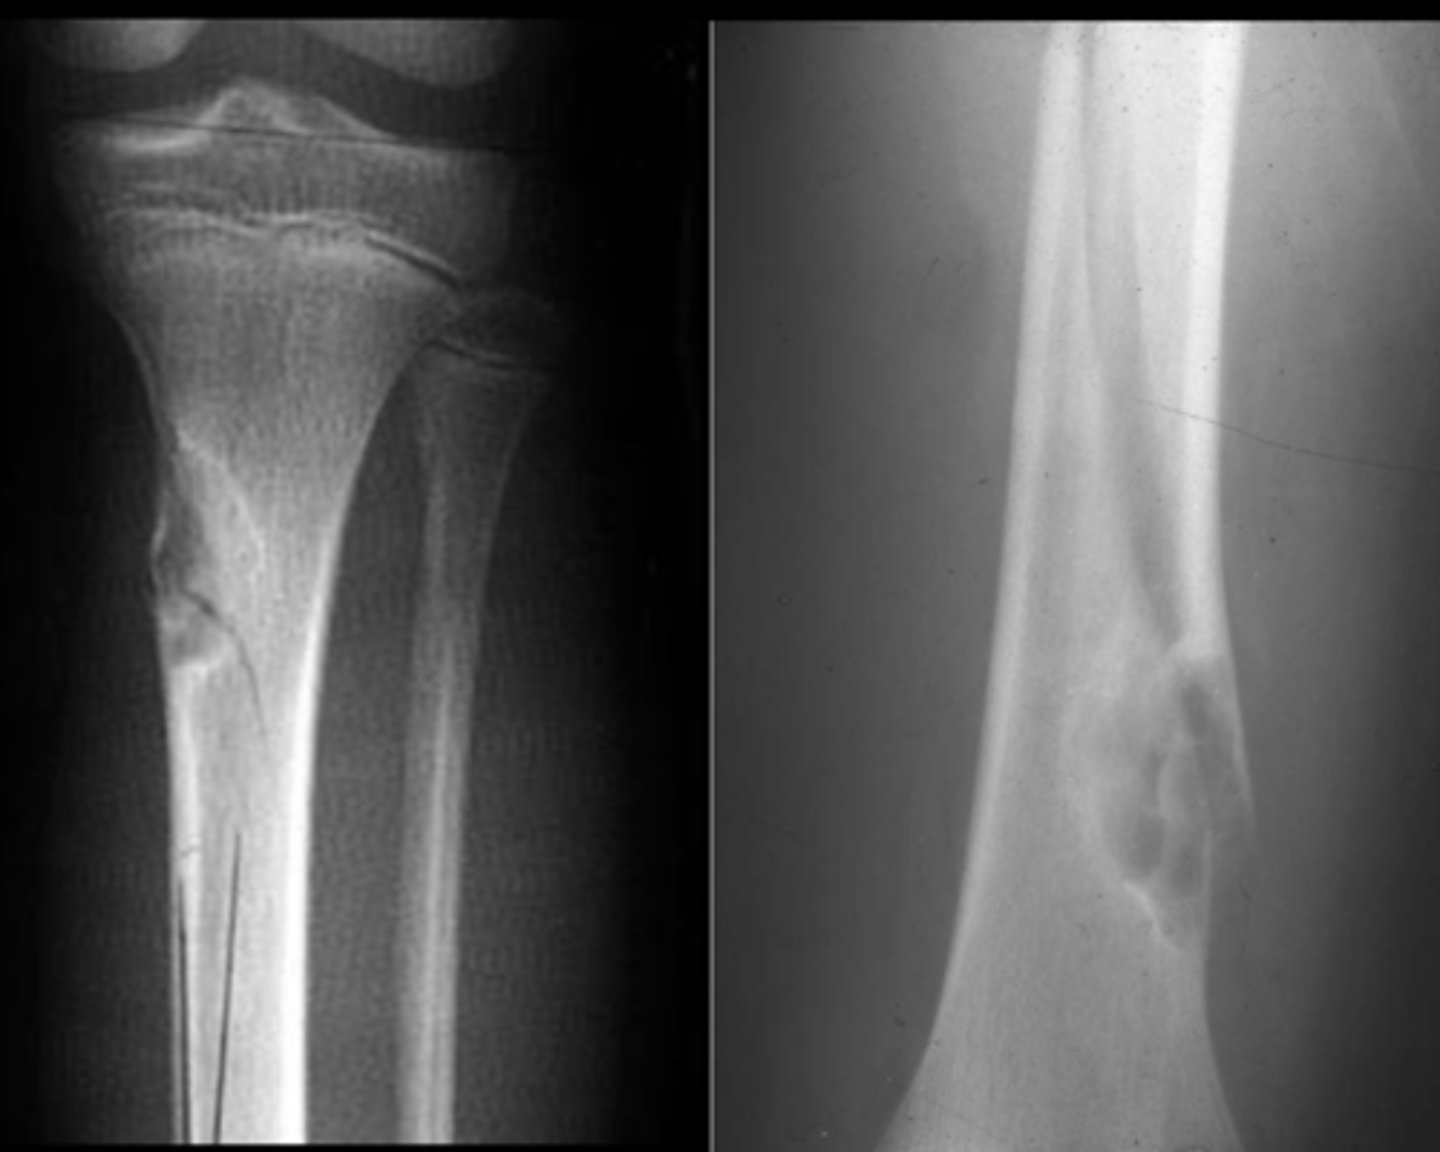

Simple bone cyst

- M:F, 2:1

- 3-14 y.o.

- Asymptomatic until fracture

- Proximal humerus (50%)

- Proximal femur (25%)

- Metaphyseal

- Migrate from physis with growth

- Mildly expansile

- Geographic

- Pseudoloculated

- Metaphyseal

- Central

- 30-40% recurrence

State the radiographic features of simple bone cyst